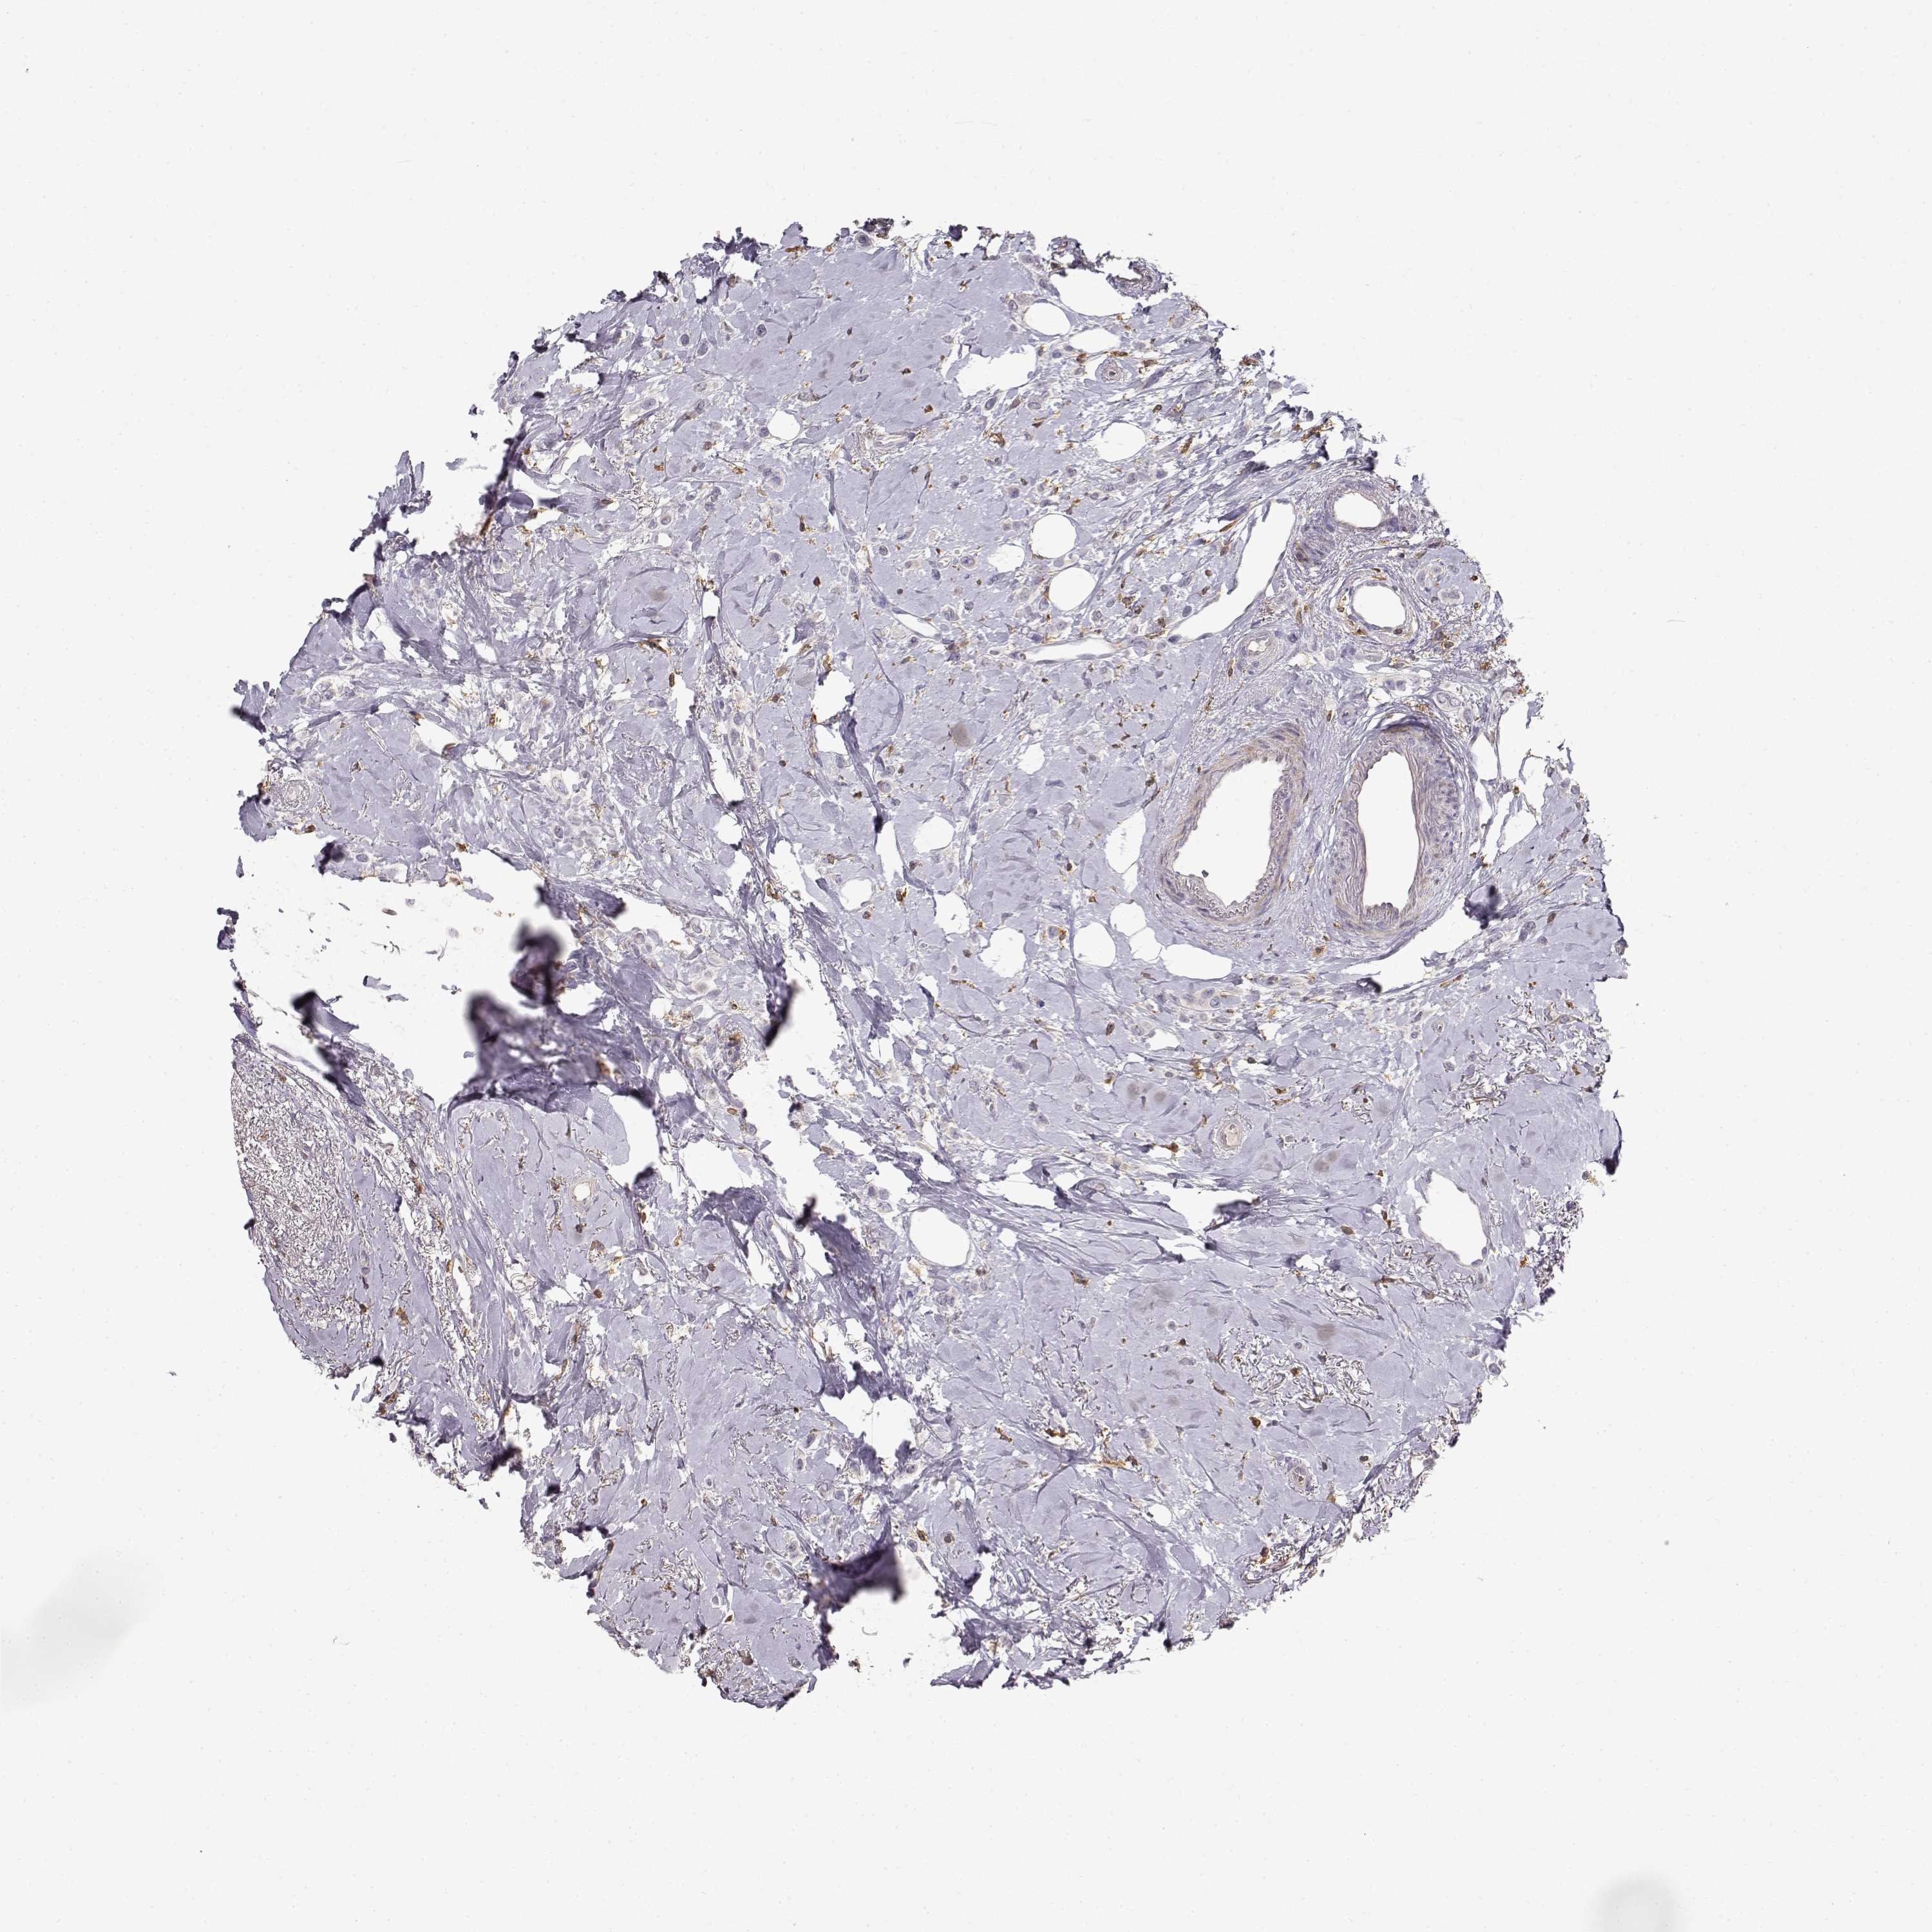

CANCER BREAST CANCER Show tissue menu

BRCA TCGA BRCA VALIDATION PROTEIN EXPRESSION